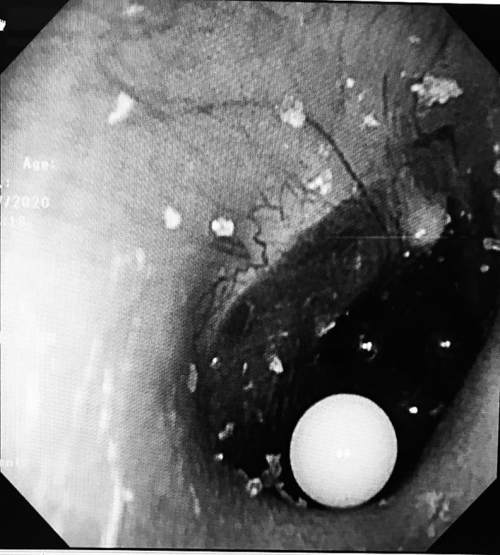

了解了情况后,医生为淘淘做了电子耳内窥镜检查,发现淘淘的右耳内有4颗彩色的小圆粒,位置都贴近了鼓膜,而且小圆粒填满了耳道。因为这是吸水弹珠,医生平时在门诊用的常规无创水冲洗法不可行,最终只能在全麻的情况下,为淘淘进行异物取出术。

耳道内发现的吸水弹珠

已经取出的吸水弹珠

手术开始两分钟后,离鼓膜最远的白色弹珠被顺利取出。“第一颗取得还算顺利,但是取另外3颗就有点困难了,剩下的3颗小珠子相互挤压,与耳道壁及鼓膜紧密接触,我们只能用耵聍钩从珠子前方、下方寻找缝隙,从里往外将弹珠带出。”李莉萍说,经过一番努力,剩下的3颗弹珠也被顺利取出。